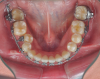

Fig 8. A class III adult male patient required surgical orthodontic treatment. The patient had anterior and posterior crossbites and required leveling of a deep curve of Spee during presurgical orthodontics.

Figure 8

Fig 9. A class III adult male patient required surgical orthodontic treatment. The patient had anterior and posterior crossbites and required leveling of a deep curve of Spee during presurgical orthodontics.

Figure 9

Fig 10. A class III adult male patient required surgical orthodontic treatment. The patient had anterior and posterior crossbites and required leveling of a deep curve of Spee during presurgical orthodontics.

Figure 10